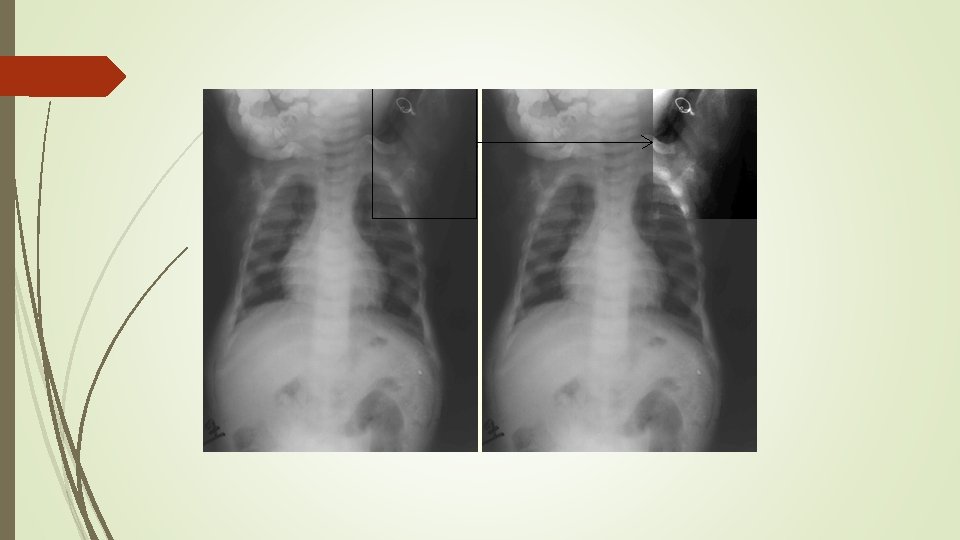

Radiographic Evaluation of Osteomalacia In Study 3, a skeletal survey was conducted at baseline to identify osteomalaciarelated fractures and pseudofractures. Osteomalacia-related fractures are defined as atraumatic lucencies extending across both bone cortices and pseudofractures are defined as atraumatic lucencies extending across one cortex. There were 52% of patients who had either active (unhealed) fractures (12%) or active pseudofractures (47%) at baseline. The active fractures and pseudofractures were predominantly located in the femurs, tibia/fibula, and metatarsals of the feet. Assessment of these active fracture/pseudofracture sites at week 24 demonstrated a higher rate of complete healing in the CRYSVITA group compared to placebo as shown in Table 8. During treatment through week 24, a total of 6 new fractures or pseudofractures appeared in 68 patients receiving CRYSVITA, compared to 8 new abnormalities in 66 patients receiving placebo

Looser zone (pseudofracture)